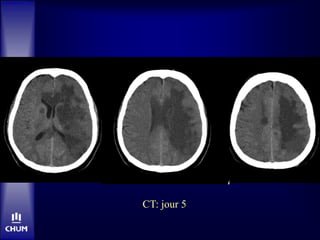

CT C- à 9h47

CT C- à 48 heures

Congé jour 5 avec NIHSS 1

CT: jour 5